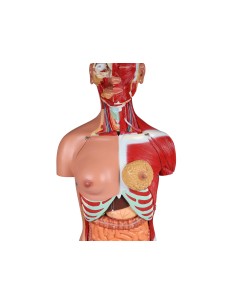

3B Scientific, Torse bisexuel, modèle de luxe, séparable en 20 parties B32

3B Scientific, Torse bisexuel, modèle de luxe, séparable en 20 parties B32

3B Scientifique, torse bisexuel japonais, décomposable en 18 parties B32/4

3B Torse scientifique, africain bisexuel, décomposable en 24 parties B37

3B Scientific, mini torse humain sans tête, décomposable en 9 parties B20